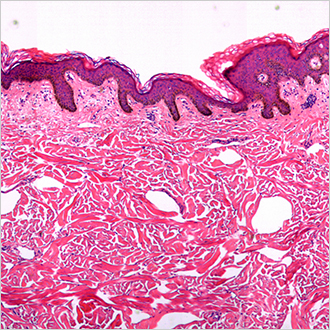

TM-Microscopy

Deze oplossing maakt optimalisering mogelijk van de verspreiding van en de toegang tot anatomisch-pathologische beelden: recuperatie, opslag en ter beschikking stellen van beelden via de TM-Microscopy-viewer. Zo wordt gezorgd voor een diagnose van hoge kwaliteit door een betere diagnose van monsters en een betere uitwisseling tussen pathologen. Lees meer?